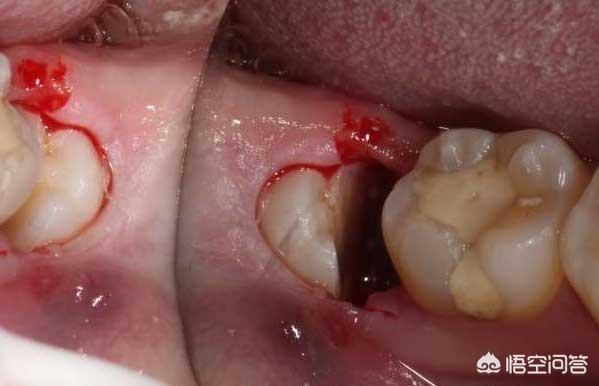

一般拔完智齿后不管有没有拆线,都是会形成牙槽窝,到了第十天炎症已经消退,虽然洞口经常塞入食物残渣,但饭后漱口基本能清洁掉,正常情况下牙槽窝在3个月左右都能愈合长平。

较大的创口将其拉拢缝合,前期一周后初步恢复,由于牙槽窝难以清洁到,很多时候洞口厌氧菌会滋生发臭,要注意当人体抵抗下降时,一碰辛辣等刺激性食物,炎症还可能会复发,甚至引起三叉神经痛或头痛。